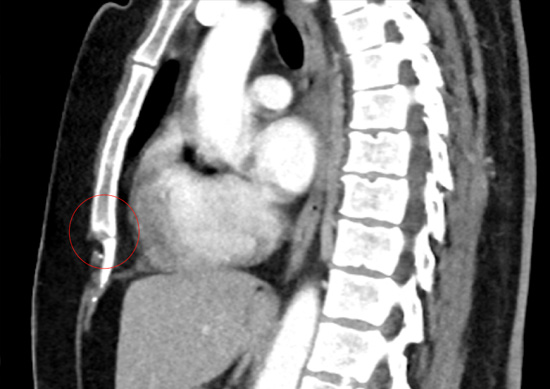

Chest CT scan following fall of an acute costochondral facture (red circle)